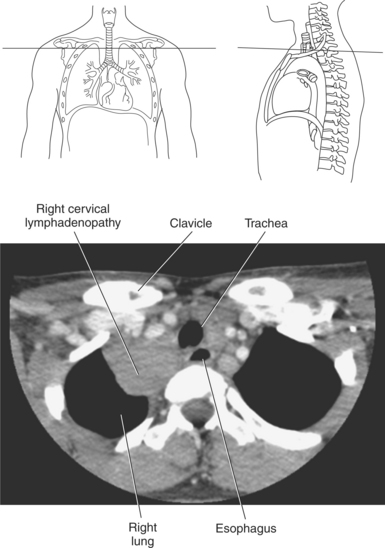

Lymph nodes in the mediastinum are generally clustered around the great vessels, esophagus, bronchi, and carina. Mediastinal lymph nodes are classified according to their location and are grouped into 14 regional nodal stations for use in lung cancer staging (Figure 6.29 and Table 6.2). Lymph vessels and nodes can be difficult to visualize in cross section unless they are enlarged as a result of an abnormality (Figures 6.30 and 6.31).

The three main branches of the aortic arch are the brachiocephalic trunk, left common carotid artery, and left subclavian artery (Figure 6.84). The brachiocephalic (innominate) trunk is the first major vessel and the largest branch arising from the aortic arch. It ascends obliquely to the upper border of the right sternoclavicular joint, where it divides into the right common carotid and right subclavian arteries (Figures 6.85 and 6.86). The right common carotid artery ascends the neck lateral to the trachea to the level of C4, where it divides into the right external and internal carotid arteries. The right subclavian artery curves posterior to the clavicle into the axillary region, where it becomes the right axillary artery. The left common carotid artery is the second vessel to branch from the aortic arch. It arises just behind the left sternoclavicular joint and ascends into the neck along the left side of the trachea to the level of C4, where it bifurcates into the left external and internal carotid arteries. The left subclavian artery arises from the aortic arch posterior to the left common carotid artery and arches laterally toward the axilla in a manner similar to that of the right subclavian artery, where it continues as the left axillary artery (Figures 6.85 through 6.88). The right and left internal thoracic arteries arise from the respective subclavian artery at the base of the neck. They run deep to the ribs, just lateral to the sternum, to supply blood to the anterior portion of the thorax (Figure 6.89). The common carotid arteries supply blood to the head and neck, whereas the subclavian arteries supply blood to the upper extremities.

The superior vena cava receives blood from the head and neck via the internal and external jugular veins and from the upper extremities via the subclavian veins (Figures 6.84 and 6.90). The subclavian veins arise from the axillary veins and course posterior to the clavicles. They receive blood from the external jugular veins before uniting with the internal jugular veins behind the sternoclavicular joints, where they continue as the brachiocephalic veins. The left brachiocephalic vein courses across the midline, anterior to the branches of the aorta, to unite with the right brachiocephalic vein just posterior to the costal cartilage of the right first rib. The union of the two brachiocephalic veins forms the superior vena cava, which empties into the right atrium of the heart (Figures 6.75 and 6.76).